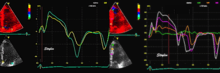

Tissue Doppler echocardiography (Also called Tissue Doppler Imaging - TDI or Tissue Velocity Imaging - TVI) is a Medical ultrasound technology mainly used in Echocardiography that measures the velocity of the heart muscle or myocardium through the phases of one or more heartbeats by the Doppler effect (frequency shift) of the reflected ultrasound. The technique is the same as for Doppler echocardiography, measuring flow velocities. Tissue signals however, have higher amplitude and lower velocities, and the signals are extracted by using different filter and gain settings. Like Doppler flow, Tissue Doppler can be acquired both by spectral analysis (Spectral density estimation) as pulsed Doppler [1] and by the Autocorrelation technique as colour Tissue Doppler [2] (Duplex ultrasonography). While pulsed Doppler only acquires the velocity at one point at a time, colour Doppler can acquire simultaneous pixel velocity values across the whole imaging field. Pulsed Doppler on the other hand, is more robust against noise, as peak values are measured on top of the spectrum, and are unaffected of the presence of clutter (stationary reverberation noise).

Pulsed wave spectral Tissue Doppler has become a universal tool that is part of the general echocardiographic examination. Like any other echocardiographic measurement, measures by tissue Doppler should be interpreted in the context of the whole examination. The velocity curves are in general taken from the base of the mitral annulus at the insertion of the mitral leaflets, in the septal and lateral points of the four chamber view, and eventually the anterior and inferior points of the two-chamber views. For the right ventricle it is customary to use the lateral point of the tricuspid annulus only.Averaging peak velocities from the septal and lateral point has become common, although it has been shown that averaging all four points mentioned above, gives significantly less variability[3]

The method measures annular velocities to and from the probe during the heart cycle.

Annular velocities summarises the longitudinal contraction of the ventricle during systole, and elongation during diastole. Peak velocities are commonly used.